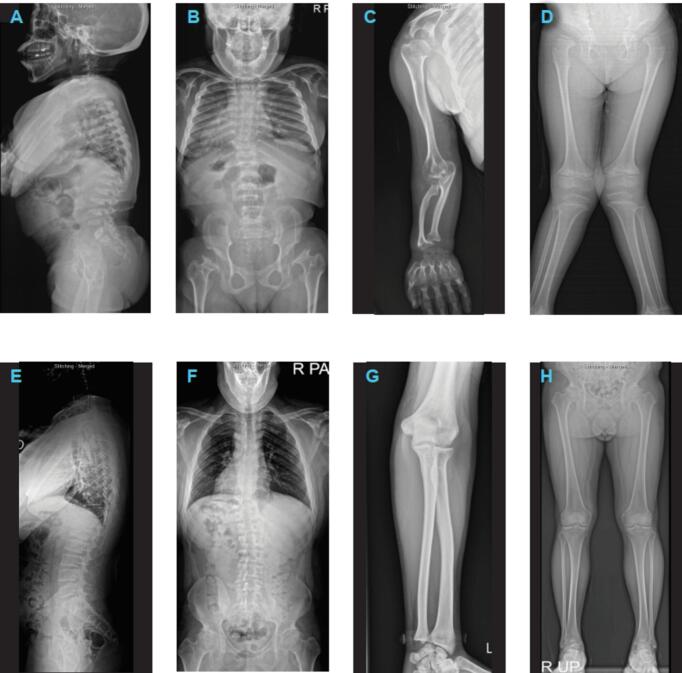

粘多糖病(MPS) IVA (Morquio A综合征)是一种常染色体隐性溶酶体贮积症,由影响n -乙酰半乳糖胺-6-硫酸酯酶(EC 3.1.6.4, GALNS)的突变引起。酶替代疗法(ERT)已被证明可以改善MPS IVA患者的身体表现、生活质量和呼吸功能;然而,由于MPS IVA的罕见性,有关韩国患者特征的数据有限。这项回顾性研究报告了临床、放射学、生化和分子方面的发现,并分析了长期临床结果,该研究来自单一中心最大的韩国MPS IVA患者队列。分析了来自14个家庭的17例患者(58.8%为女性;诊断年龄中位数[范围]5.2[1.8-33.7]岁)。大多数患者(64.7%)被分类为重度表型,23%为中度表型,11.8%为轻度表型。初诊时骨骼表现和影像学异常包括步态异常(35.3%)、身材矮小(23.5%)、胸部畸形(23.5%)、脊柱侧凸(17.6%)、脊柱后凸(11.8%)、面部畸形(6%)、髋部疼痛(6%)和腿部畸形(6%)。鉴定出12种不同的GALNS突变。患者接受ERT治疗的中位(范围)为7.4年(3.0-12.1年)。12例患者达到最终成人身高,所有重度/中度表型患者身材矮小(MPS IVA经ERT治疗后),未发现新的安全性问题。

Mucopolysaccharidosis (MPS) IVA (Morquio A syndrome) is an autosomal recessive lysosomal storage disorder caused by a mutation affecting the enzyme N-acetylgalactosamine-6-sulfatase (EC 3.1.6.4, GALNS). Enzyme replacement therapy (ERT) has been shown to improve physical performance, quality of life, and respiratory function in patients with MPS IVA; however, owing to the rarity of MPS IVA, data on Korean patient characteristics are limited. This retrospective study reports clinical, radiographic, biochemical, and molecular findings, and analyzes long-term clinical outcomes, from the largest cohort of Korean patients with MPS IVA in a single center. The analysis included 17 patients from 14 families (58.8 % females; median [range] age at diagnosis 5.2 [1.8–33.7] years). The majority of patients (64.7 %) were classified as having a severe phenotype, 23 % had an intermediate phenotype, and 11.8 % had an attenuated phenotype. Skeletal manifestations and radiologic abnormalities at initial diagnosis included gait abnormality (35.3 %), short stature (23.5 %), chest deformity (23.5 %), scoliosis (17.6 %), kyphosis (11.8 %), dysmorphic face (6 %), hip pain (6 %), and leg deformity (6 %). Twelve different GALNS mutations were identified. Patients received ERT for a median (range) 7.4 years (3.0–12.1). Twelve patients reached final adult height, and all patients with the severe/intermediate phenotype had short stature (<3rd percentile). Hemiepiphysiodesis was the most common surgical intervention among patients with the severe/intermediate phenotype. Drug-related adverse events (urticaria, rash, and anaphylaxis) were reported in four patients but were managed with antihistamines or desensitization. At follow-up, patients experienced improvements in functional independence measure score, ejection fraction, and the 6-min walk test compared with the pre-treatment baseline. This study provides real-world evidence for long-term stabilization of functional independence, endurance, and respiratory function among patients with MPS IVA treated with ERT, with no new safety concerns identified.